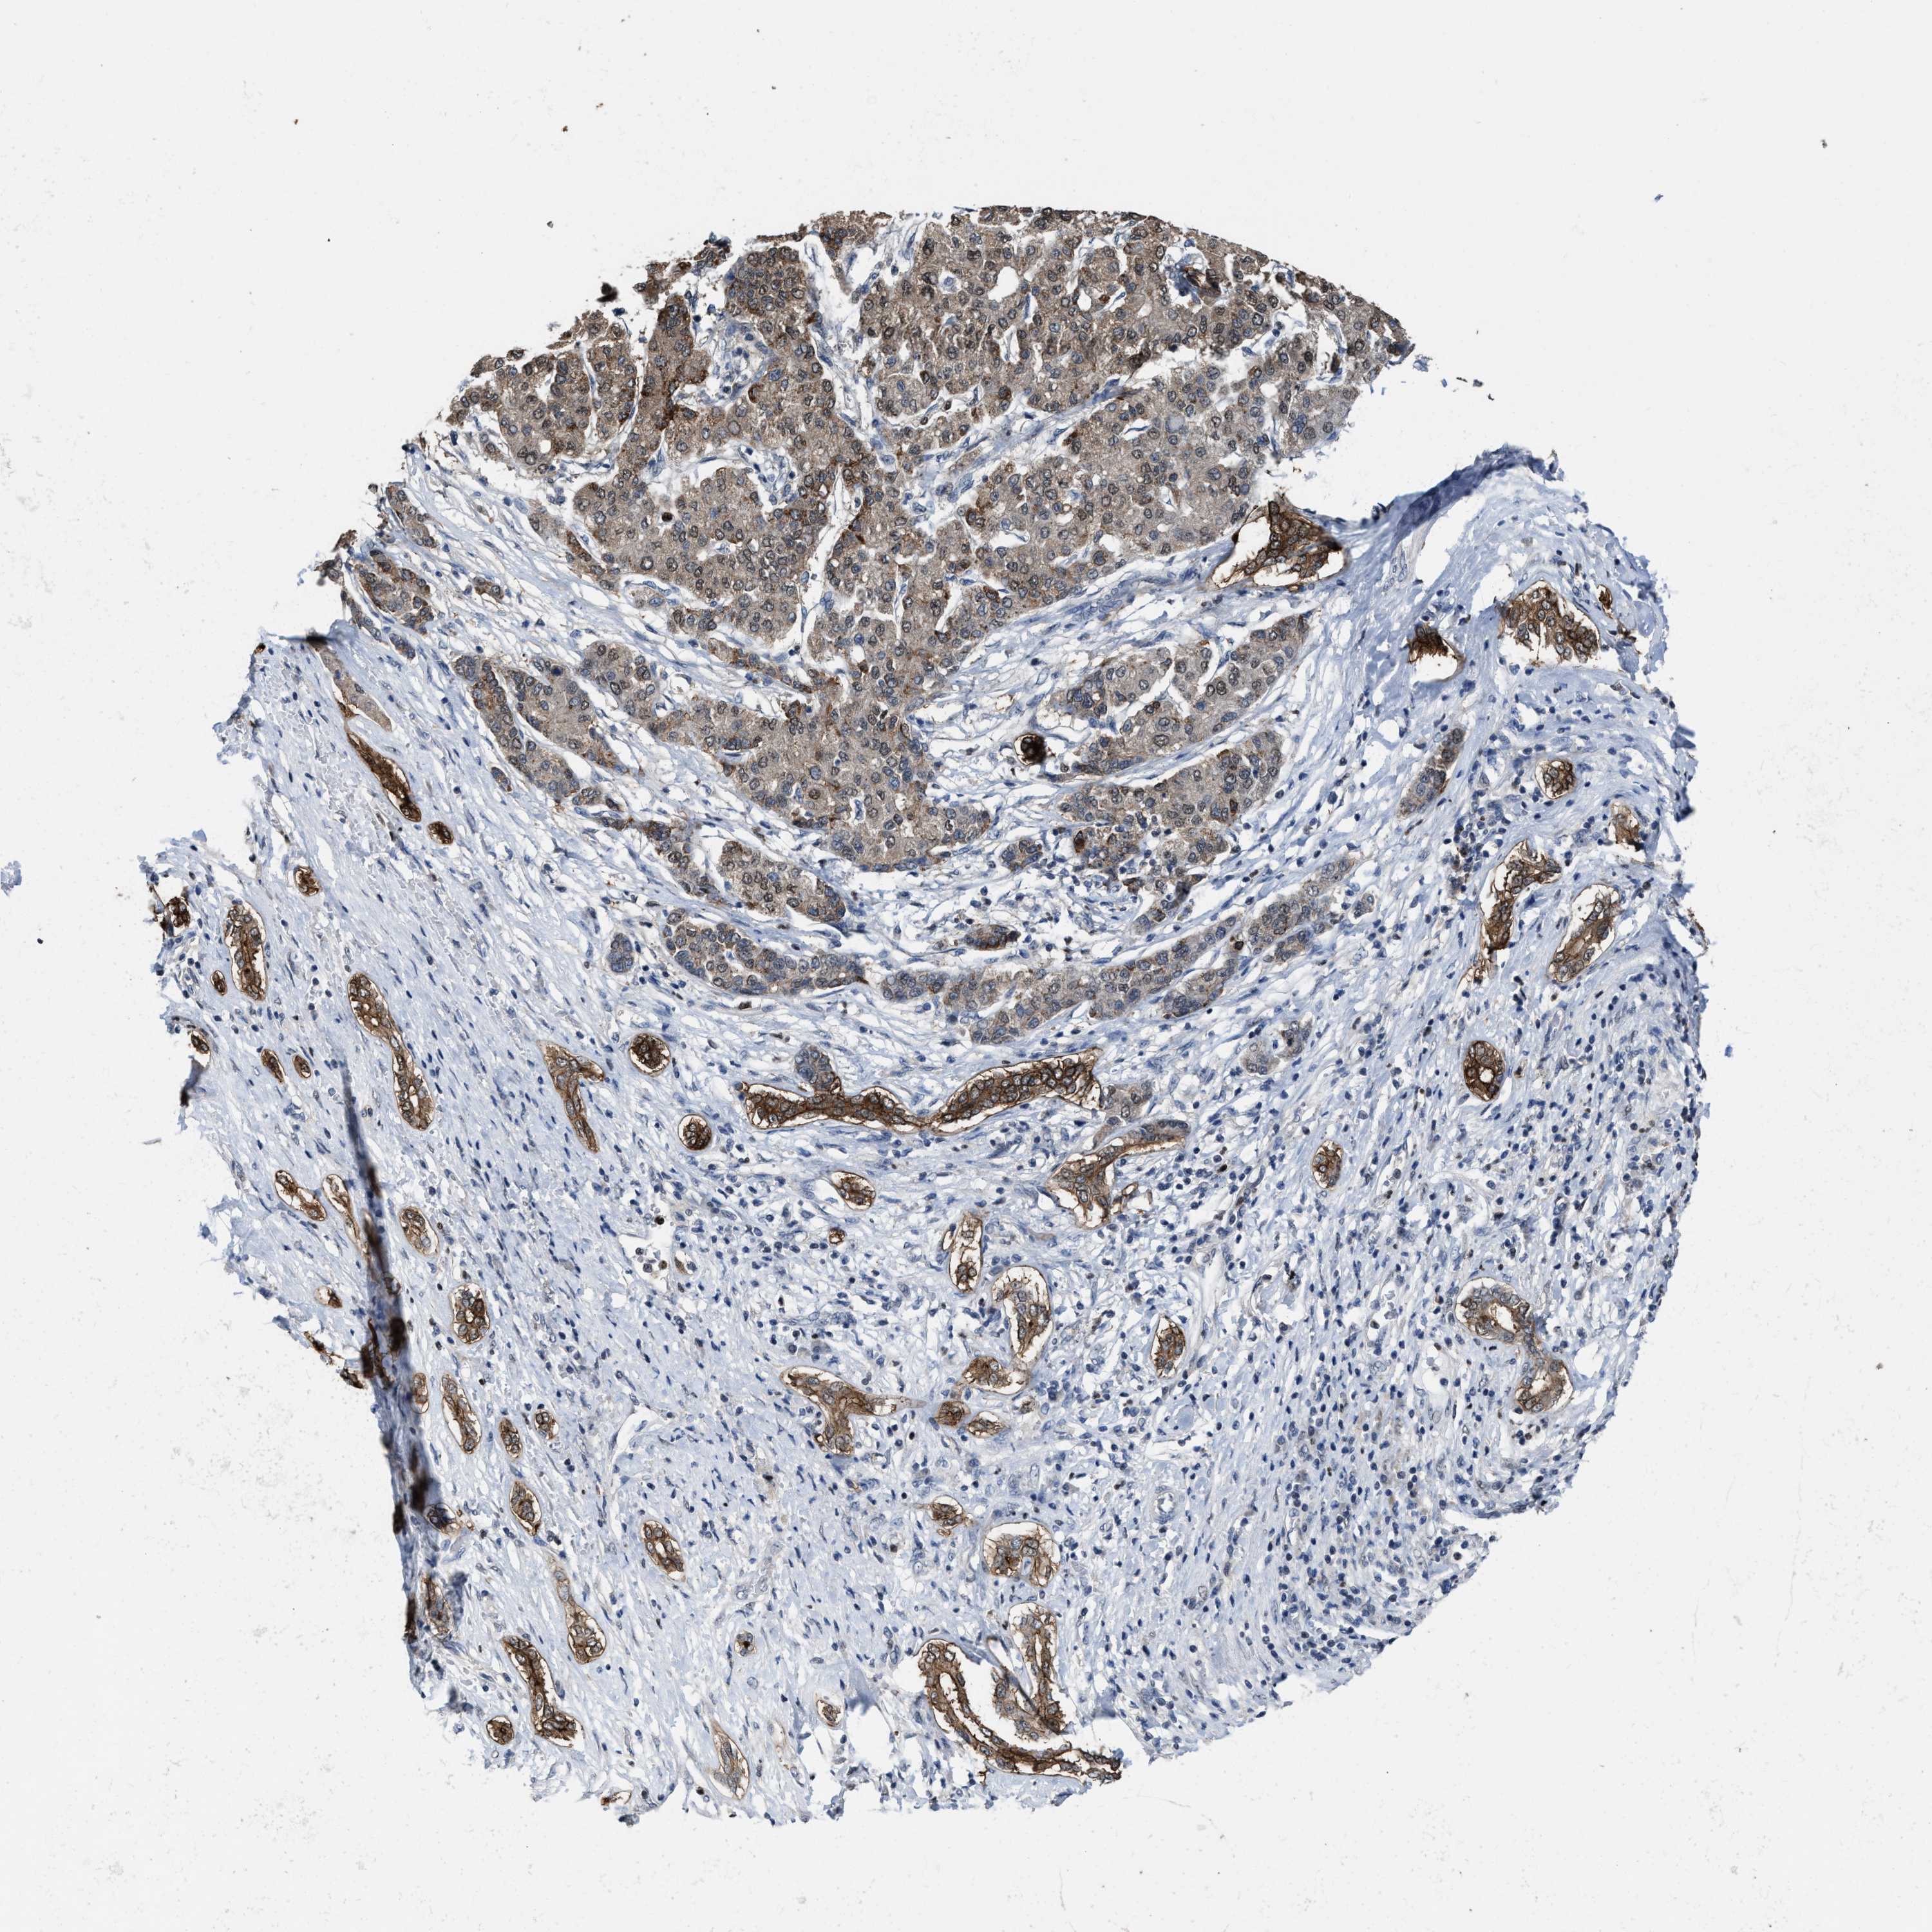

LIVER CANCER - Protein expressioni

A mouse-over function shows sample information and annotation data. Click on an image to view it in a full screen mode. Samples can be filtered based on level of antibody staining by selecting one or several of the following categories: high, medium, low and not detected. The assay and annotation is described here.

Note that samples used for immunohistochemistry by the Human Protein Atlas do not correspond to samples in the TCGA dataset.

Antibody stainingi

Antibody staining in the annotated cell types in the current human tissue is reported as not detected, low, medium, or high, based on conventional immunohistochemistry profiling in selected tissues. This score is based on the combination of the staining intensity and fraction of stained cells.

Each image is clickable and will lead to virtual microscopy that enables deeper exploration of all samples and also displays staining intensity scores, fraction scores and subcellular localization as well as patient and tissue information for each sample.

Antibody HPA020887

Staining

High

Medium

Low

Not detected

Intensity

Strong

Moderate

Weak

Negative

Quantity

>75%

75%-25%

<25%

None

Location

Nuclear

Cytoplasmic/membranous

Cytoplasmic/membranous,nuclear

Cholangiocarcinoma

Carcinoma, Hepatocellular, NOS